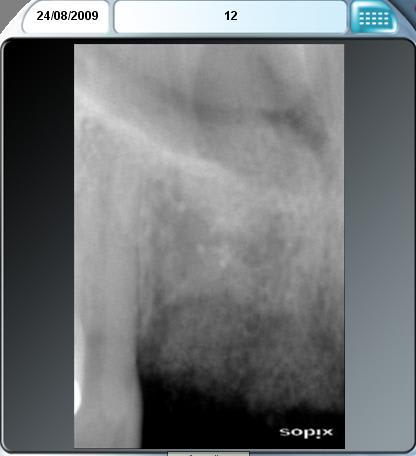

CF cas similaire antérieur avec un vrai gruyère osseux......la patiente veut aussi différer les implants pour raisons financières.

12 bilan tbr0kg - Eugenol

12 postop m665pp - Eugenol

22 bilan bew07m - Eugenol

22 postop j7az46 - Eugenol

Simp bilan ejqvaq - Eugenol

2009 08 04 rumszi - Eugenol

Simp postop iq5cd8 - Eugenol